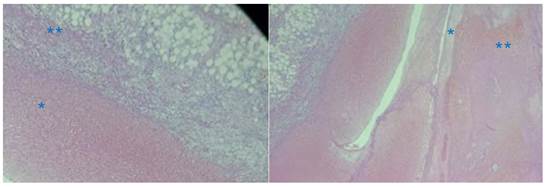

Se procedió a transfundir 2 unidades de concentrado globular, logrando un control postransfusional de hemoglobina de 12 g/dL. El hallazgo intraoperatorio macroscópico (figuras 3A, 3B) fue confirmado por el estudio anatomopatológico, evidenciándose en la microscopia la inserción de tejido trofoblástico en tejido graso epiploico (figura 4A). El examen anatomopatológico de la tumoración mostró la presencia de células de sincitiotrofoblasto en el tejido del epiplón, con una densa invasión y presencia de vellosidades en tejido graso (figura 4B).

Figura 4 estudio anatomopatológico: a vista de la inserción de tejido trofoblástico (*) en el tejido graso epiploico (**). b. tejido graso del epiplón (*), donde se halló tejido placentario (**).